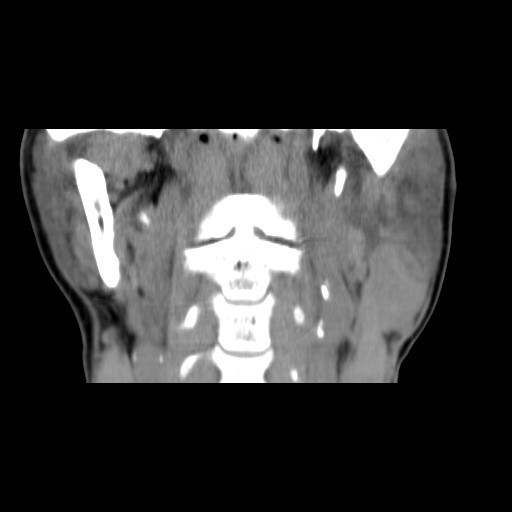

患者:男,64岁。 主诉:左耳垂下肿物1年余 病史:患者1年余前发现左耳垂下肿物,逐渐增大,与进食无关,无疼痛、麻木感,未予治疗。 体查:左右颜面部基本对称,双侧上、下颌骨未及明显异常膨隆,左耳垂下腮腺区见一膨隆肿物,大小约为4cm×3cm,边界欠清,质软,表面皮肤无红肿、破溃、出血,无触痛,皮温正常,活动度可。 辅助检查:无

诊断:左腮腺肿物(?) 治疗:入院后上颌CT平扫+增强:左侧腮腺深叶结节灶,考虑良性病变,腺淋巴瘤与多形性腺瘤鉴别,排除手术禁忌症,于2015-10-16送手术室全麻下行"左腮腺深叶肿物切除+面神经解剖+邻近皮瓣转移修复术"。术后病理提示:左腮腺肿物,符合多形性腺瘤。